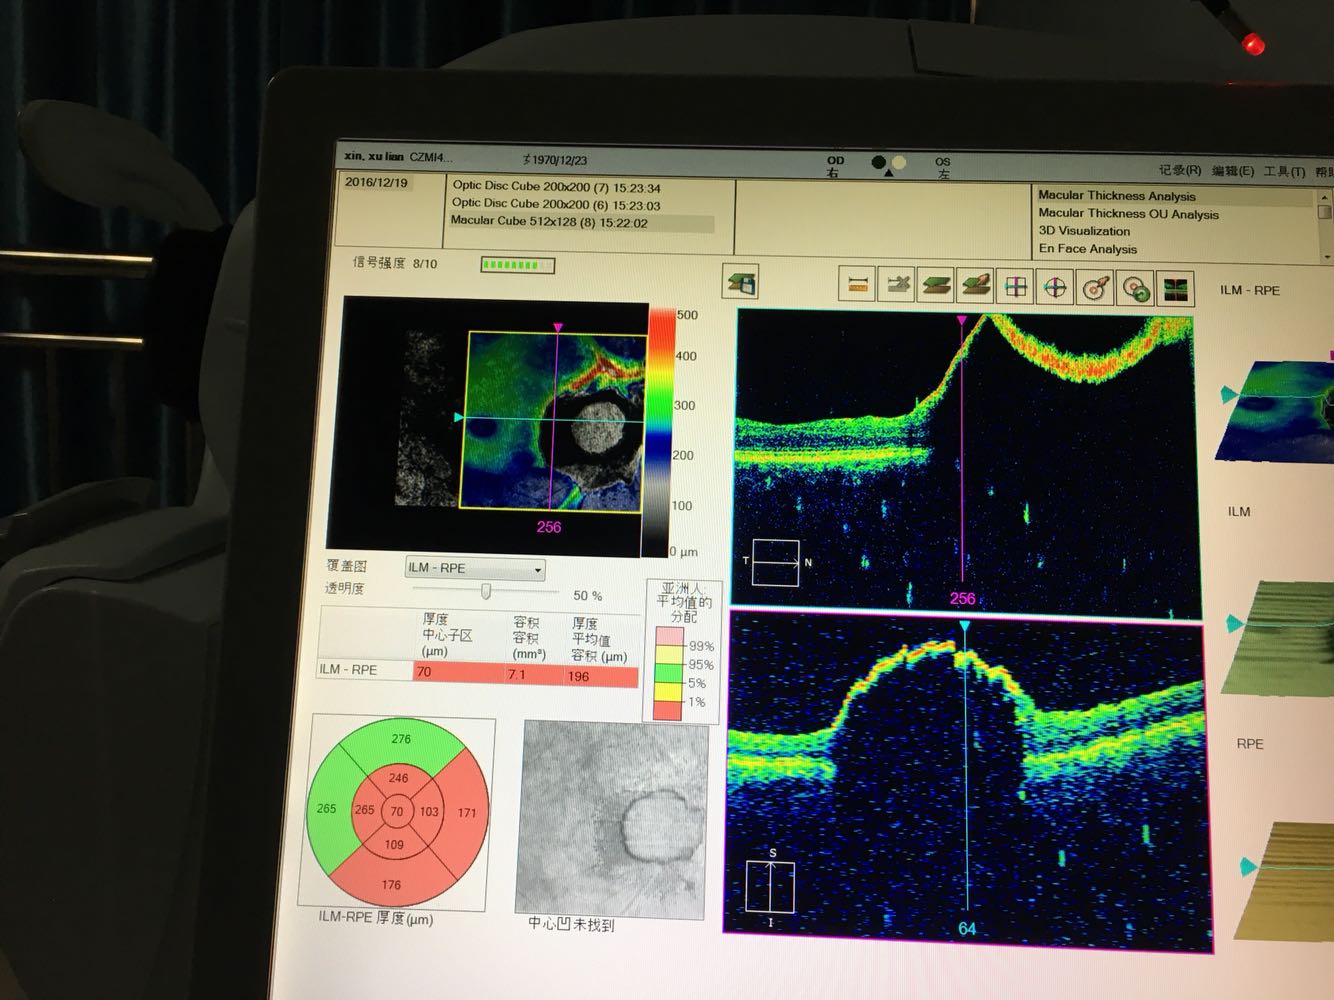

视乳头黑色素瘤

视力右眼5.0,左眼5.0,角膜明,前房正常深,瞳孔3.0mm,对光反射灵敏,晶体明,眼底左眼视乳头颞下方可见约2.5PD黑色素瘤,表面略高起,周围视网膜未见明显异常,眼压正常。

视乳头黑色素瘤,较3年前增长不明显,患者拒绝眼底照相及视野检查。